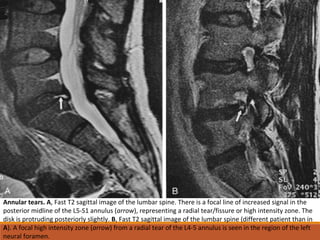

Annular tears. A, Fast T2 sagittal image of the lumbar spine. There is a focal line of increased signal in the

posterior midline of the L5-S1 annulus (arrow), representing a radial tear/fissure or high intensity zone. The

disk is protruding posteriorly slightly. B, Fast T2 sagittal image of the lumbar spine (different patient than in

A). A focal high intensity zone (arrow) from a radial tear of the L4-5 annulus is seen in the region of the left

neural foramen.

Fast T2 axial image of

L4-5 (same patient as

in B). Short, linear

segments of high

signal (arrows) are

present in the

posterolateral L4-5

disk from annular

tears in the foraminal

regions. The disks are

protruding at the

sites of the tears,

resulting in mild

bilateral foraminal

narrowing.